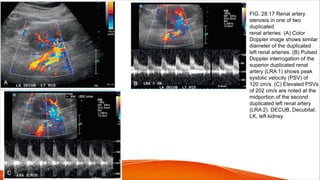

FIG. 28.17 Renal artery

stenosis in one of two

duplicated

renal arteries. (A) Color

Doppler image shows similar

diameter of the duplicated

left renal arteries. (B) Pulsed

Doppler interrogation of the

superior duplicated renal

artery (LRA 1) shows peak

systolic velocity (PSV) of

120 cm/s. (C) Elevated PSVs

of 202 cm/s are noted at the

midportion of the second

duplicated left renal artery

(LRA 2). DECUB, Decubital;

LK, left kidney